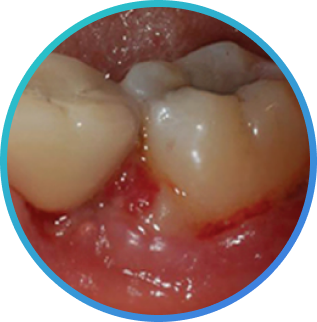

치은조직과 치조골을 자연 치아와 잇몸 형태로 형성하는 Implant

술식으로 Implant 시술을 한 부위에 식편압입을 예방 또는 최소화합니다.

- 치은조직과 치조골을 자연 치아와 잇몸 형태로 형성하는 Implant 술식으로 Implant 시술을 한 부위에 식편압입 예방 또는 최소화